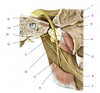

A

Zygomatic process (of temporal bone)

B

Tubercle (of temporal bone)

C

Groove for deep temporal vessels (of temporal bone)

D

Postglenoid tubercle (of temporal bone)

E

Supramastoid crest (of temporal bone)

F

Suprameatal spine (of temporal bone)

G

Opening of external acoustic meatus (of temporal bone)

H

Tympanomastoid fissure (of temporal bone)

I

Mastoid process (of temporal bone)

J

Tympanic part (of temporal bone)

K

Vaginal process (of temporal bone)

L

Styloid process (of temporal bone)

M

Angle (of mandible)

N

Ramus (of mandible)

O

Condylar process (head and neck)(of mandible)

P

Mandibular notch and coronoid process (of mandible)

Q

Anterior (surface of maxilla)

R

Infratemporal (surface of maxilla)

S

Zygomatic bone

T

Zygomatic arch

U

Frontal bone

V

Greater wing of sphenoid

W

Squamous part of temporal bone

1

Articular tubercle